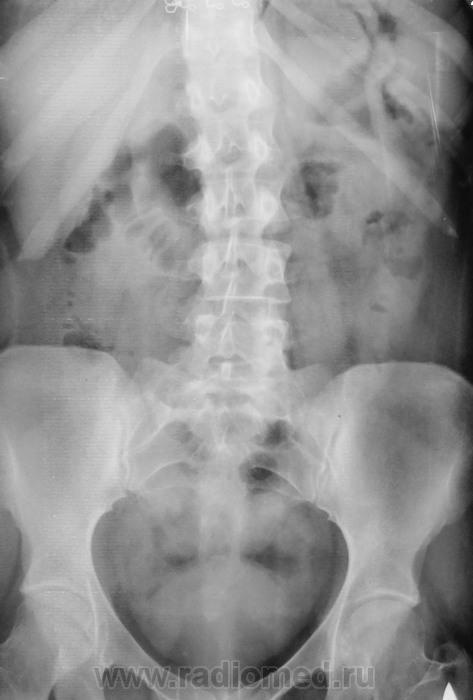

Молодая женщина направлена в рентгеновский кабинет для производства внутривенной урографии, после того, как при УЗИ исследовании был обнаружен конкремент, якобы в мочеточнике.

Беспокоят боли в поясничной области и дизурические явления в виде частого мочеиспускания. Мочеиспускания довольно частые, малыми порциями (за 20 минут - 3 раза).

Установлено, что все вышеперечисленное началось после обычных физиологических родов, ручного вмешательства не было.

Чем так сдавлен мочевой пузырь?

Камешек понятно, более уверенно справа, менее уверенно слева - желтые стрелки.

Но, что за объём давит сверху - зеленые стрелки.

Да, некоторая эктация справа имеет место быть, чем она вызвана, тем мелким конкрементом который бы давно плюхнулся в мочевой пузырь, или чем то другим?

Что это "светлое", помеченное желтыми стрелками, газосодержание раздавливаемое "объёмом" в прямой кишке?

Что это более "темное", помеченное бирюзовыми стрелками, нависшее над "светлым?

Перед исследованием пациентка мочилась, сом отправил посмотрев обзорку. Во время исследования (за 15 минут) еще два раза помочилась.

Что давит, какие предположения уважаемые коллеги?

Совсем мне не понятно почему мочеточник справа (частично эктазированный) контрастированный туго на всем протяжении, не прослеживается на участке, помеченном красными стрелками, как раз перед так называемым "конкрементом" в правом устье, хотя должно было бы быть наоборот. Может эта часть отдавлена, раздевлена? Чем?

Кроме матки, больше здесь нечему быть. Не думаю, что содержит газ в указанных местах, скорее - не полностью шарообразная.

Матка поддавливает мочеточник, не создается адекватное гидродинамическое давление над камнем, и он торчит в устье.

Камень устья правого мочеточника. Справа гидронефроз I ст. Остальное норма. Кишка+матка, больше ничего не угляделось.

1.За 9 месяцев беременности матка увеличивается в размерах более чем в 500 раз, а после родов постепенно возвращается к своему прежнему состоянию.

2.Для возвращения матки в добеременные размеры в среднем требуется 1,5-2,5 месяца.

3.Но бывает, что матка после родов не сокращается или сокращается очень медленно. Точнее, чаще всего встречается именно сниженная способность матки к сокращению (гипотония матки), а полный паралич маточных мышц (атония) встречается реже.

4.Увеличенная матка в данном случае сдавливает мочеточники.

5. Чем быстрее матка вернется к своим прежним размерам, тем быстрее купируется данная колика.